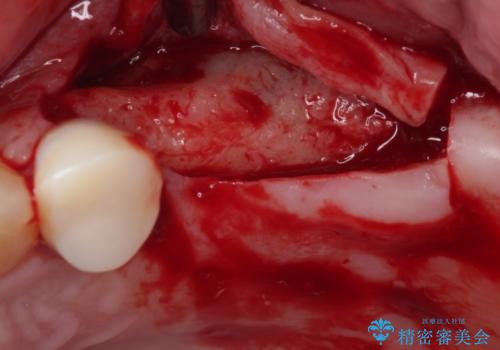

上顎は左右ともに骨が少ない状態であり、特殊なドリルを用いた歯槽骨の拡大や自家骨挙上などを行いながらインプラントを埋入していくこととしました。